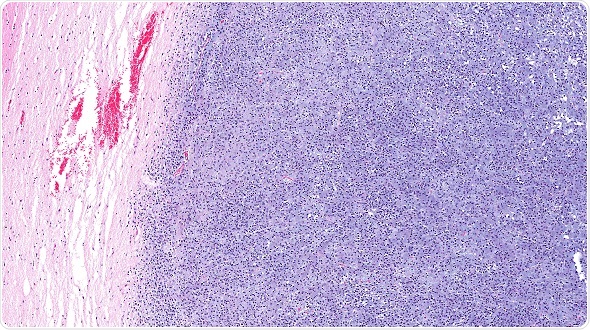

Image

MRI: Brain tumour at right parietal lobe.

© Puwadol Jaturawuttichai / Shutterstock.com